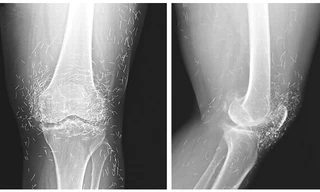

TPO - Các bác sĩ tại Đại học Boston vô cùng sốc khi phát hiện hàng trăm chiếc kim châm cứu trong đầu gối của một phụ nữ 65 tuổi người Hàn Quốc sau khi chụp X –quang. Bà cho biết trước đây đã châm cứu để chữa bệnh xương khớp.